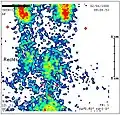

Bestehen Zweifel an der Diagnose, kommen zur Differentialdiagnostik eine Schilddrüsenszintigraphie sowie eine Probeentnahme durch Feinnadelaspiration mit anschließender histologischer Untersuchung infrage. Beide Verfahren gehören bei diesem Krankheitsbild nicht zur Routinediagnostik und sind nur in Einzelfällen, insbesondere bei atypischen Verläufen, erforderlich. Die Jodaufnahme, die quantitativ mit der Schilddrüsenszintigraphie gemessen werden kann, ist durch die entzündungsbedingte Jod-Transport-Störung und den verminderten TSH-Spiegel meist stark reduziert. Insbesondere in einer thyreotoxischen Phase ist die Jodaufnahme massiv verringert (24-Stunden-Aufnahme von 123Jod unter 5 Prozent), was bei differentialdiagnostischen Überlegungen hilfreich ist, beispielsweise zur Abgrenzung eines Morbus Basedow.[16] Bei der Feinnadelbiopsie (Feinnadelaspiration) wird sonographisch gesteuert Schilddrüsengewebe mit einer dünnen Nadel entnommen (Biopsie), das anschließend in der Pathologie histologisch untersucht wird.

Schilddrüsenszintigrafie bei Subakuter Thyreoiditis: verminderter Uptake.

Schilddrüsenszintigrafie bei Subakuter Thyreoiditis: verminderter Uptake. -